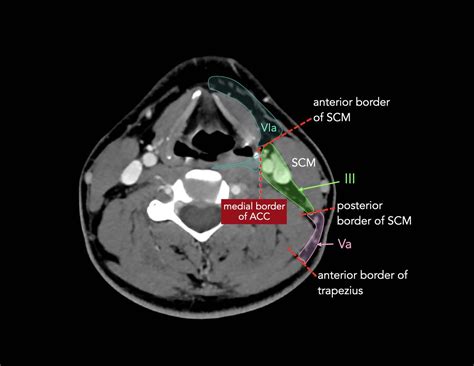

Level V: Posterior Triangle

Level V lymph nodes are located in the posterior triangle of the neck, bounded by the sternocleidomastoid muscle, trapezius muscle, and clavicle. These nodes drain lymph from the scalp, posterior neck, and upper back. They are important for detecting infections and malignancies in these areas.

Level VI: Anterior Compartment

Level VI lymph nodes are situated in the anterior compartment of the neck, between the hyoid bone and the suprasternal notch. These nodes drain lymph from the thyroid gland, larynx, and central compartment of the neck. They are crucial for evaluating thyroid cancers and other malignancies in the anterior neck region.